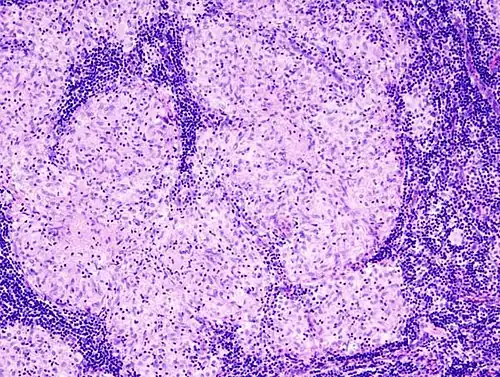

Histopathology

Sarcoidosis is characterized by the formation of non-necrotizing ("non-caseating") granulomas in various organs and tissues.[95] Giant cells, specifically Langhans giant cells, are often seen in sarcoidosis.[96] Schaumann bodies seen in sarcoidosis are calcium and protein inclusions inside of giant cells as part of a granuloma.[97] Asteroid bodies can be seen in sarcoidosis.[97] Hamazaki–Wesenberg bodies can be seen in lymph nodes and more rarely in lung biopsies with sarcoidosis and are inclusion bodies of lysosomes with protein, glycoprotein and iron.[98]

-

Sarcoidosis in a lymph node -